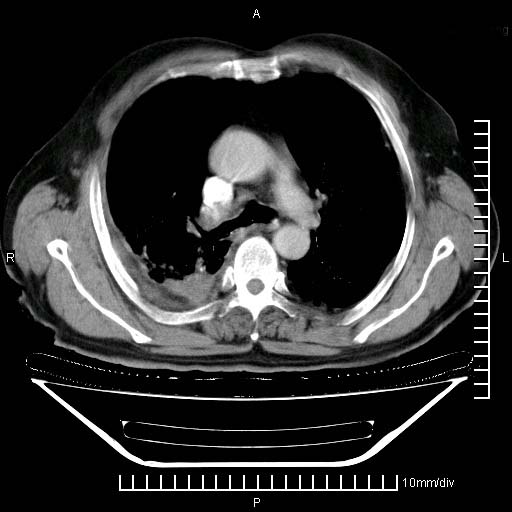

既往肺结核,近10几天,咳嗽,咳痰,右侧胸痛,疼痛较明显,右上肺斑块考虑结核灶胸膜粘连,增强,可惜动脉期没有定好,未见强化,可延迟4分后又见较明显强化,中心见低密度影,如果说结核是边缘强化,可这个灶强化的面积挺大的,让人很挠头。

延迟4分后